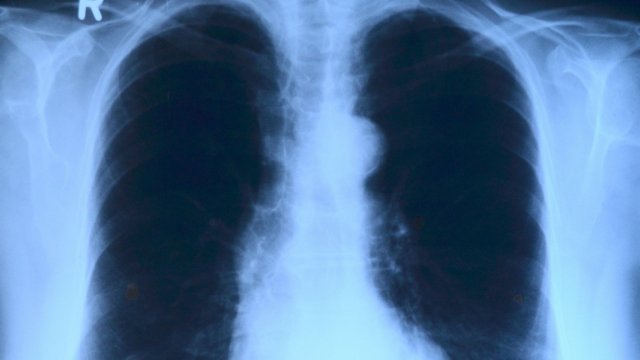

Новите случаи на COVID-19 през последното денонощие са 266, има един починал вследствие на болестта, показват данните, публикувани в Единния информационен портал.

Новите случаи са открити с помощта на 1904 теста, което означава, че делът на положителните тестове е 14 процента.

Общият брой на починалите от началото на пандемията достигна 38 476. Активни са 3715 случая, хоспитализирани са 364 от тях, като 42 са били приети в болница през последния ден.

В интензивно отделение са настанени 24 души с диагноза "COVID-19".

За последните 24 часа са били излекувани 151 пациенти, с което общият им брой достигна 1 273 515. Поставените дози от ваксина за последното денонощие са 3424, с което общият брой на поставените дози достигна 4 629 119.